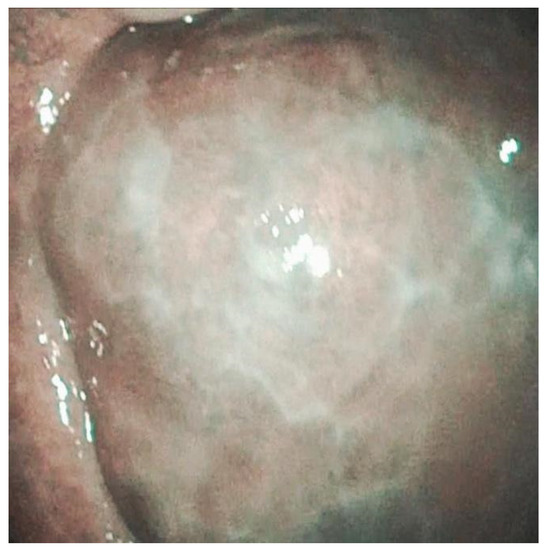

| 3 | Right buccal mucosa and lateral right surface of the tongue. | Leukoplakia of the right surface of the tongue with an indurated area in the lower portion. | Reticular lichenoid-like lesions on the right buccal mucosa without suspicious of malignancy | Evidence of intrapapillary capillary loops. | Epitelial verrucous hyperplasia |